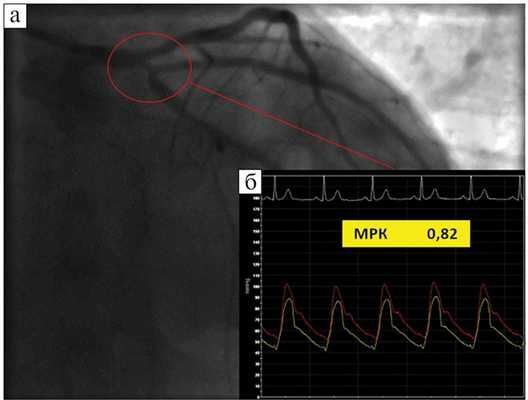

Клинический пример. Больной И., 55 лет, в течение последних 3 мес жаловался на боли ангинозного характера при физических нагрузках средней интенсивности. Около 2 мес назад при КГ выявлен устьевой стеноз ОА пограничного характера (68%). Факторы риска развития ИБС: курение, гипертоническая болезнь, мужской пол.

При нагрузочной ЭхоКГ на пике нагрузки выявлена преходящая гипокинезия базальных нижнебокового и переднебокового сегментов с распространением на средний переднебоковой сегмент ЛЖ. В то же время по данным ОФЭКТ миокарда отмечены признаки ишемии миокарда, индуцированной нагрузкой, в области боковых сегментов ЛЖ (см. рис. 5 и далее). Таким образом, по результатам СНС-ВИМ выявлена ишемия миокарда ЛЖ боковой локализации, индуцированная нагрузкой. Толерантность к физическим нагрузкам оказалось средней (8 METs).

После контрольной ангиографии левой КА (рис. 6, а) у пациента в области устья ОА определено значение МРК 0,82 (рис. 6, б). На основании результатов обследования сделан вывод о функциональной значимости исследуемого коронарного стеноза.

Рис. 6. Пример определения МРК у больного И., 55 лет. а — ангиограмма левой КА: устьевой 68% стеноз ОА (обведен красным кругом); б — результат определения МРК=0,82.